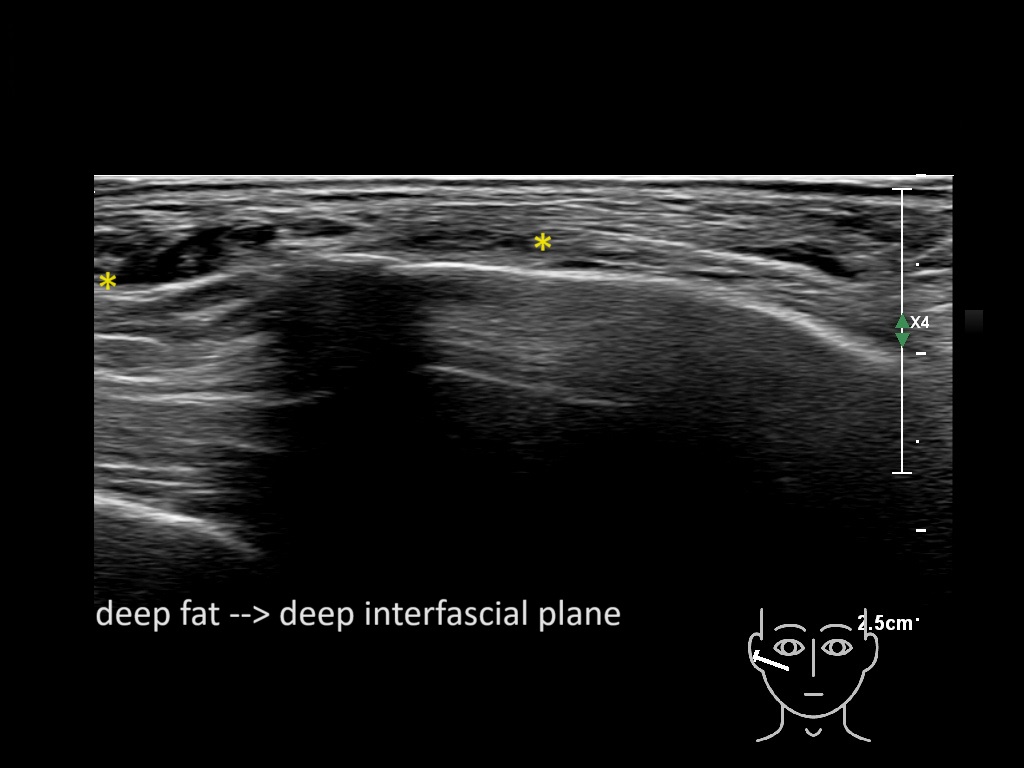

Filler behavior - Temple zygoma US

Study the first image to recognize the different layers. If you are sure about the layers, swipe to the second image to view the answer (if applicable).

Hover over an image to view the secondary image or click on the image title for more information.